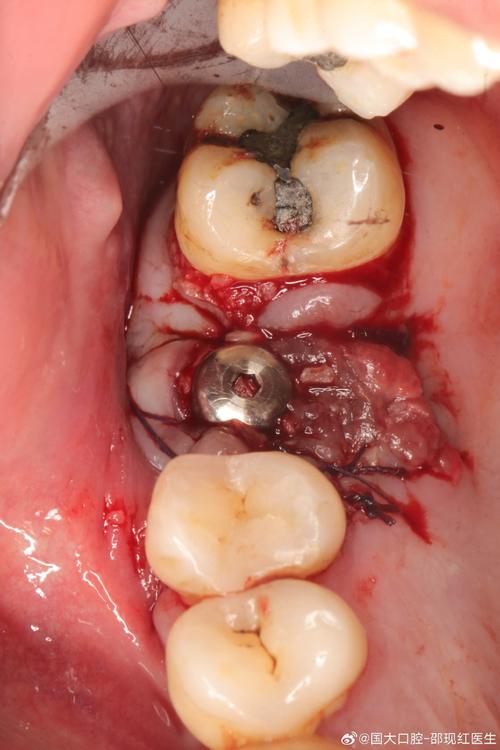

(图片来源网络,侵删) -